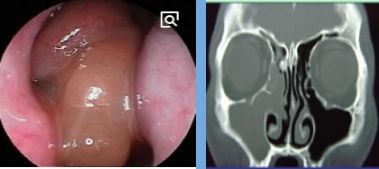

2、影像学检查:CT扫描显示窦口鼻道复合体或鼻窦粘膜病变。

- 副鼻窦X线检查,CT(冠状位、轴位)检查已常规应用。

正常鼻窦CT

鼻窦炎轴位CT

鼻窦炎冠状CT